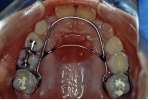

| 治療中